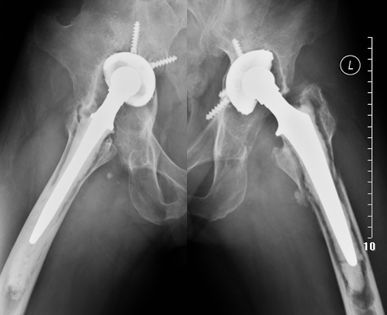

45岁,女性患者,2010年4、5月前于外院行分别行双侧全髋关节置换术,术后1年开始出现双髋轻微疼痛,未予系统诊治;2014年3月来我院就诊,只能卧床,被动强迫体位,双髋活动严重受限,X片如上。

诊断为双侧人工髋关节假体周围感染,于2014年4月分别行双侧髋关节假体取出、病灶清理、抗生素骨水泥占位器旷置术

感染控制后于2014年7月、8月分别行左、右侧复杂髋关节翻修术(Spcer占位器取出,钛网固定、打压植骨、翻修假体植入,右侧联合使用大粗隆钢板)。术后4年复查照片如上,打压植骨血管化,髋关节假体稳定,位置角度良好,患者功能恢复良好。